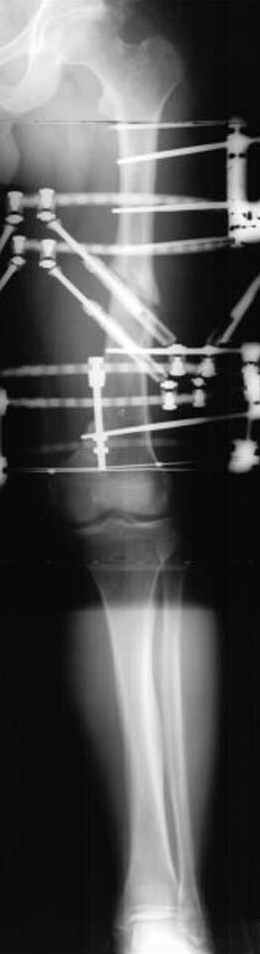

5:24 Рентгенограмма таза, вызывают врача ортопеда (снимок N1), его диагноз: закрытый переломо-вывих правого тазабедренного сустава, получает добро на закрытую репозицию в приемном отделении

5:38 Дважды неудачная попытка закрытой репозиции в приемном отделении

N 2

6:20 ответстенный врач принимает решение о репозиции в условиях операционной, предупреждаются родственники и больной, что при неудачной закрытой репозиции, о возможности открытой репозиции и фиксации задней стенки вертлужной впадины.

7:30 начало операции, больной на спине, попытка репозиции после анестезии N3, укладка больного на боку, доступ Kocher- Langenbeck, состояние седалищнего нерва около 2.5см кровоподтек, через joistick головка бедра приподнята, освобовождение сустава, фрагмент заднего края более 3х4 см репонирован на свое место. После промывания

сустава, репозиция вывиха (N4), фиксация фрагмента 2.7(4) мм шурупами и допольнительно реконструктивной пластиной на 8 дырок, фиксация 3.5мм шурупами проксимально и дистально.

Интраоперционные N5 косая запирательная и N6 подвздошный снимок

11:50 больной в послеоперационной, рентгенограмма N7, компьютерная томограмма в тот же день N8-10